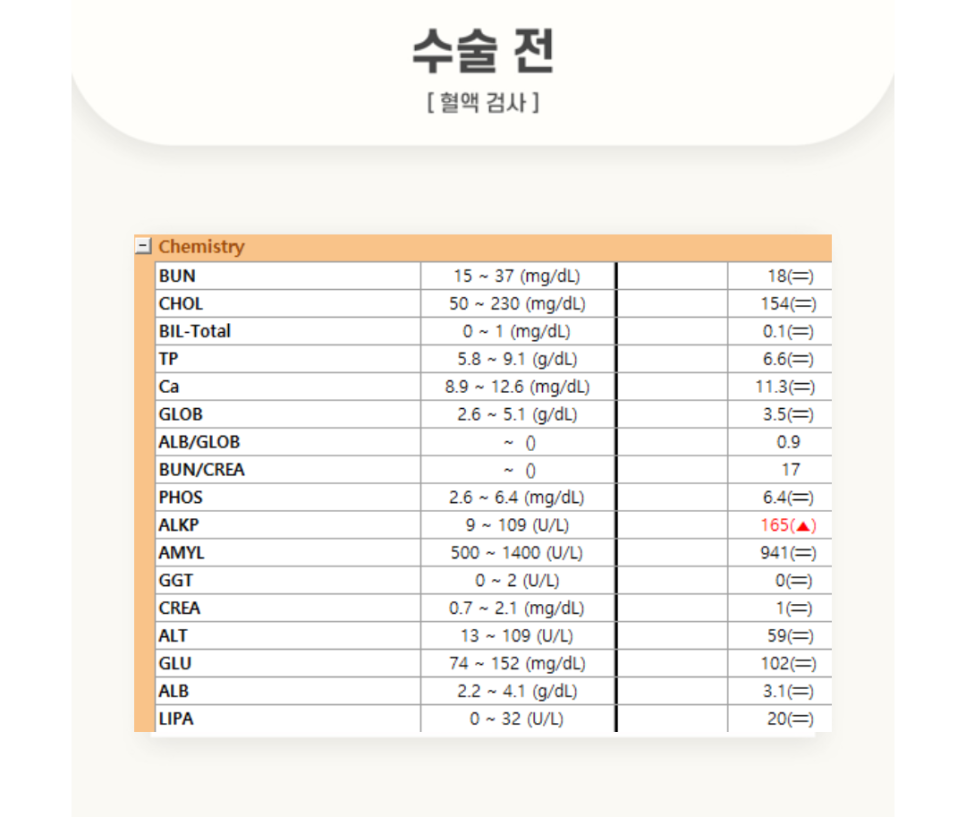

[수술 전 혈액검사]

경기동물의료원 (처인구동물병원)에 내원한 눈* 환자는, 이도내시경 검사를 위해 마취전 검사를 꼼꼼히 진행하였습니다.